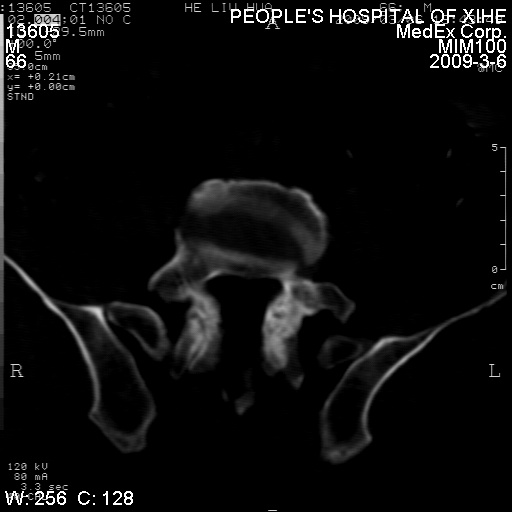

标题: CT18522:男,66岁。考虑结核有错吗 [打印本页]

标题: CT18522:男,66岁。考虑结核有错吗

x线片示:骶骨密度增高。

考虑----腰椎骶化-----退变-----椎管狭窄

腰骶椎退行性改变。

腰骶椎退行性改变,建议重建看看!

退行性变,椎体滑脱

腰椎滑脱并有退变

退行性变,椎体滑脱。建议同椎体平行进一步扫描。